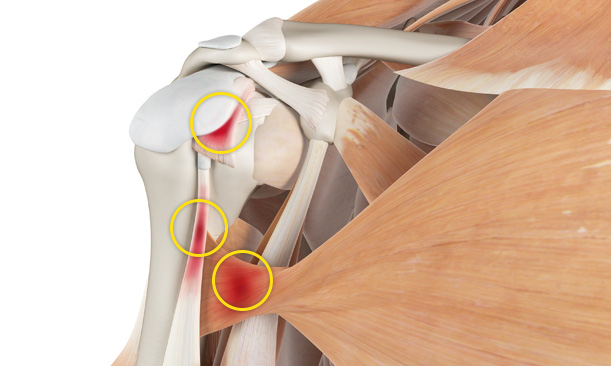

어깨충돌증후군이 발생하게 되면 회전근개에 염증이 발생하게 되고

급성 부종을 일으키게 됩니다.

어깨충돌증후군은 팔을 지속적으로 들고 일을 하는 직업군과

어깨를 많이 쓰는 스포츠 활동군에서 많이 발생합니다.

어깨의 휴식을 취하지 않고 무리하게 사용하는 경우 발생됩니다.